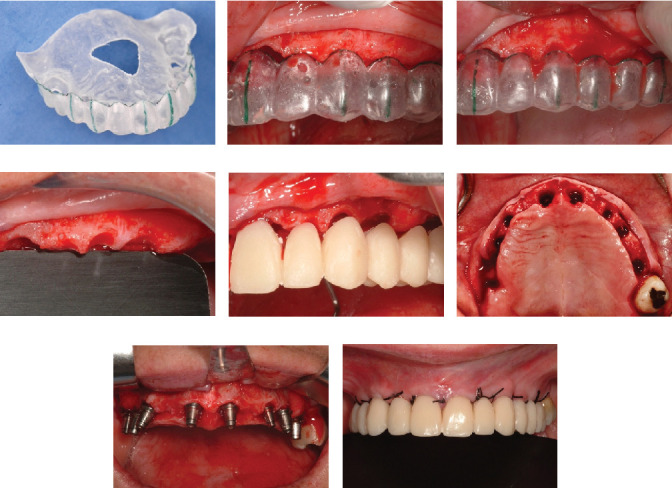

需要上颌种植体康复的部分义齿,无论是使用分段式还是夹板固定义齿,通常都需要进行三维牙位规划。这种规划可能导致牙冠边缘接触或侵蚀剩余的牙槽骨,这是以前的上牙疹的后果。上萌牙与牙周生长有关,牙周韧带和牙周骨与萌牙同时发育。在这种情况下,为了获得成功的结果,在植入假体之前进行骨重塑是至关重要的,为生物宽度创造足够的空间,这对于实现分段、种植体支持、固定的假体是必不可少的。在本病例报告中,患者接受了8个假体和4个固定部分假体,在使用假体18年后,种植体周围炎需要移除后路假体,需要在相应象限重新治疗。值得注意的是,假体之间的近端接触已经打开,可能是由于颅面继续生长和骨重塑,尽管这并不影响患者的功能。修复后的骨和软组织保持原位,近端间乳头和牙龈轮廓均保留在美观区。

Partial edentulism requiring maxillary rehabilitation with dental implants, whether using segmented or splinted fixed prostheses, often involves three-dimensional tooth position planning. This planning can lead to crown margins that either contact or encroach upon the remaining alveolar bone, a consequence of previous supraeruption. Supraeruption is associated with periodontal growth, where the periodontal ligament and bone develop concurrently with the erupting tooth. For successful outcomes in such cases, it is crucial to perform bone recontouring before implant placement, creating adequate space for the biological width, which is essential for achieving a segmented, implant-supported, fixed prosthesis. In the patient described in this case report, who received eight implants and four fixed partial prostheses, peri-implantitis required the removal of a posterior implant after 18 years of prosthesis use, necessitating retreatment in the corresponding quadrant. Notably, interproximal contacts between the prostheses had opened, likely due to continued craniofacial growth and bone remodeling, although this did not affect the patient's functionality. The recontoured bone and soft tissues maintained their position, preserving both the interproximal papillae and gingival contour in the esthetic zone.